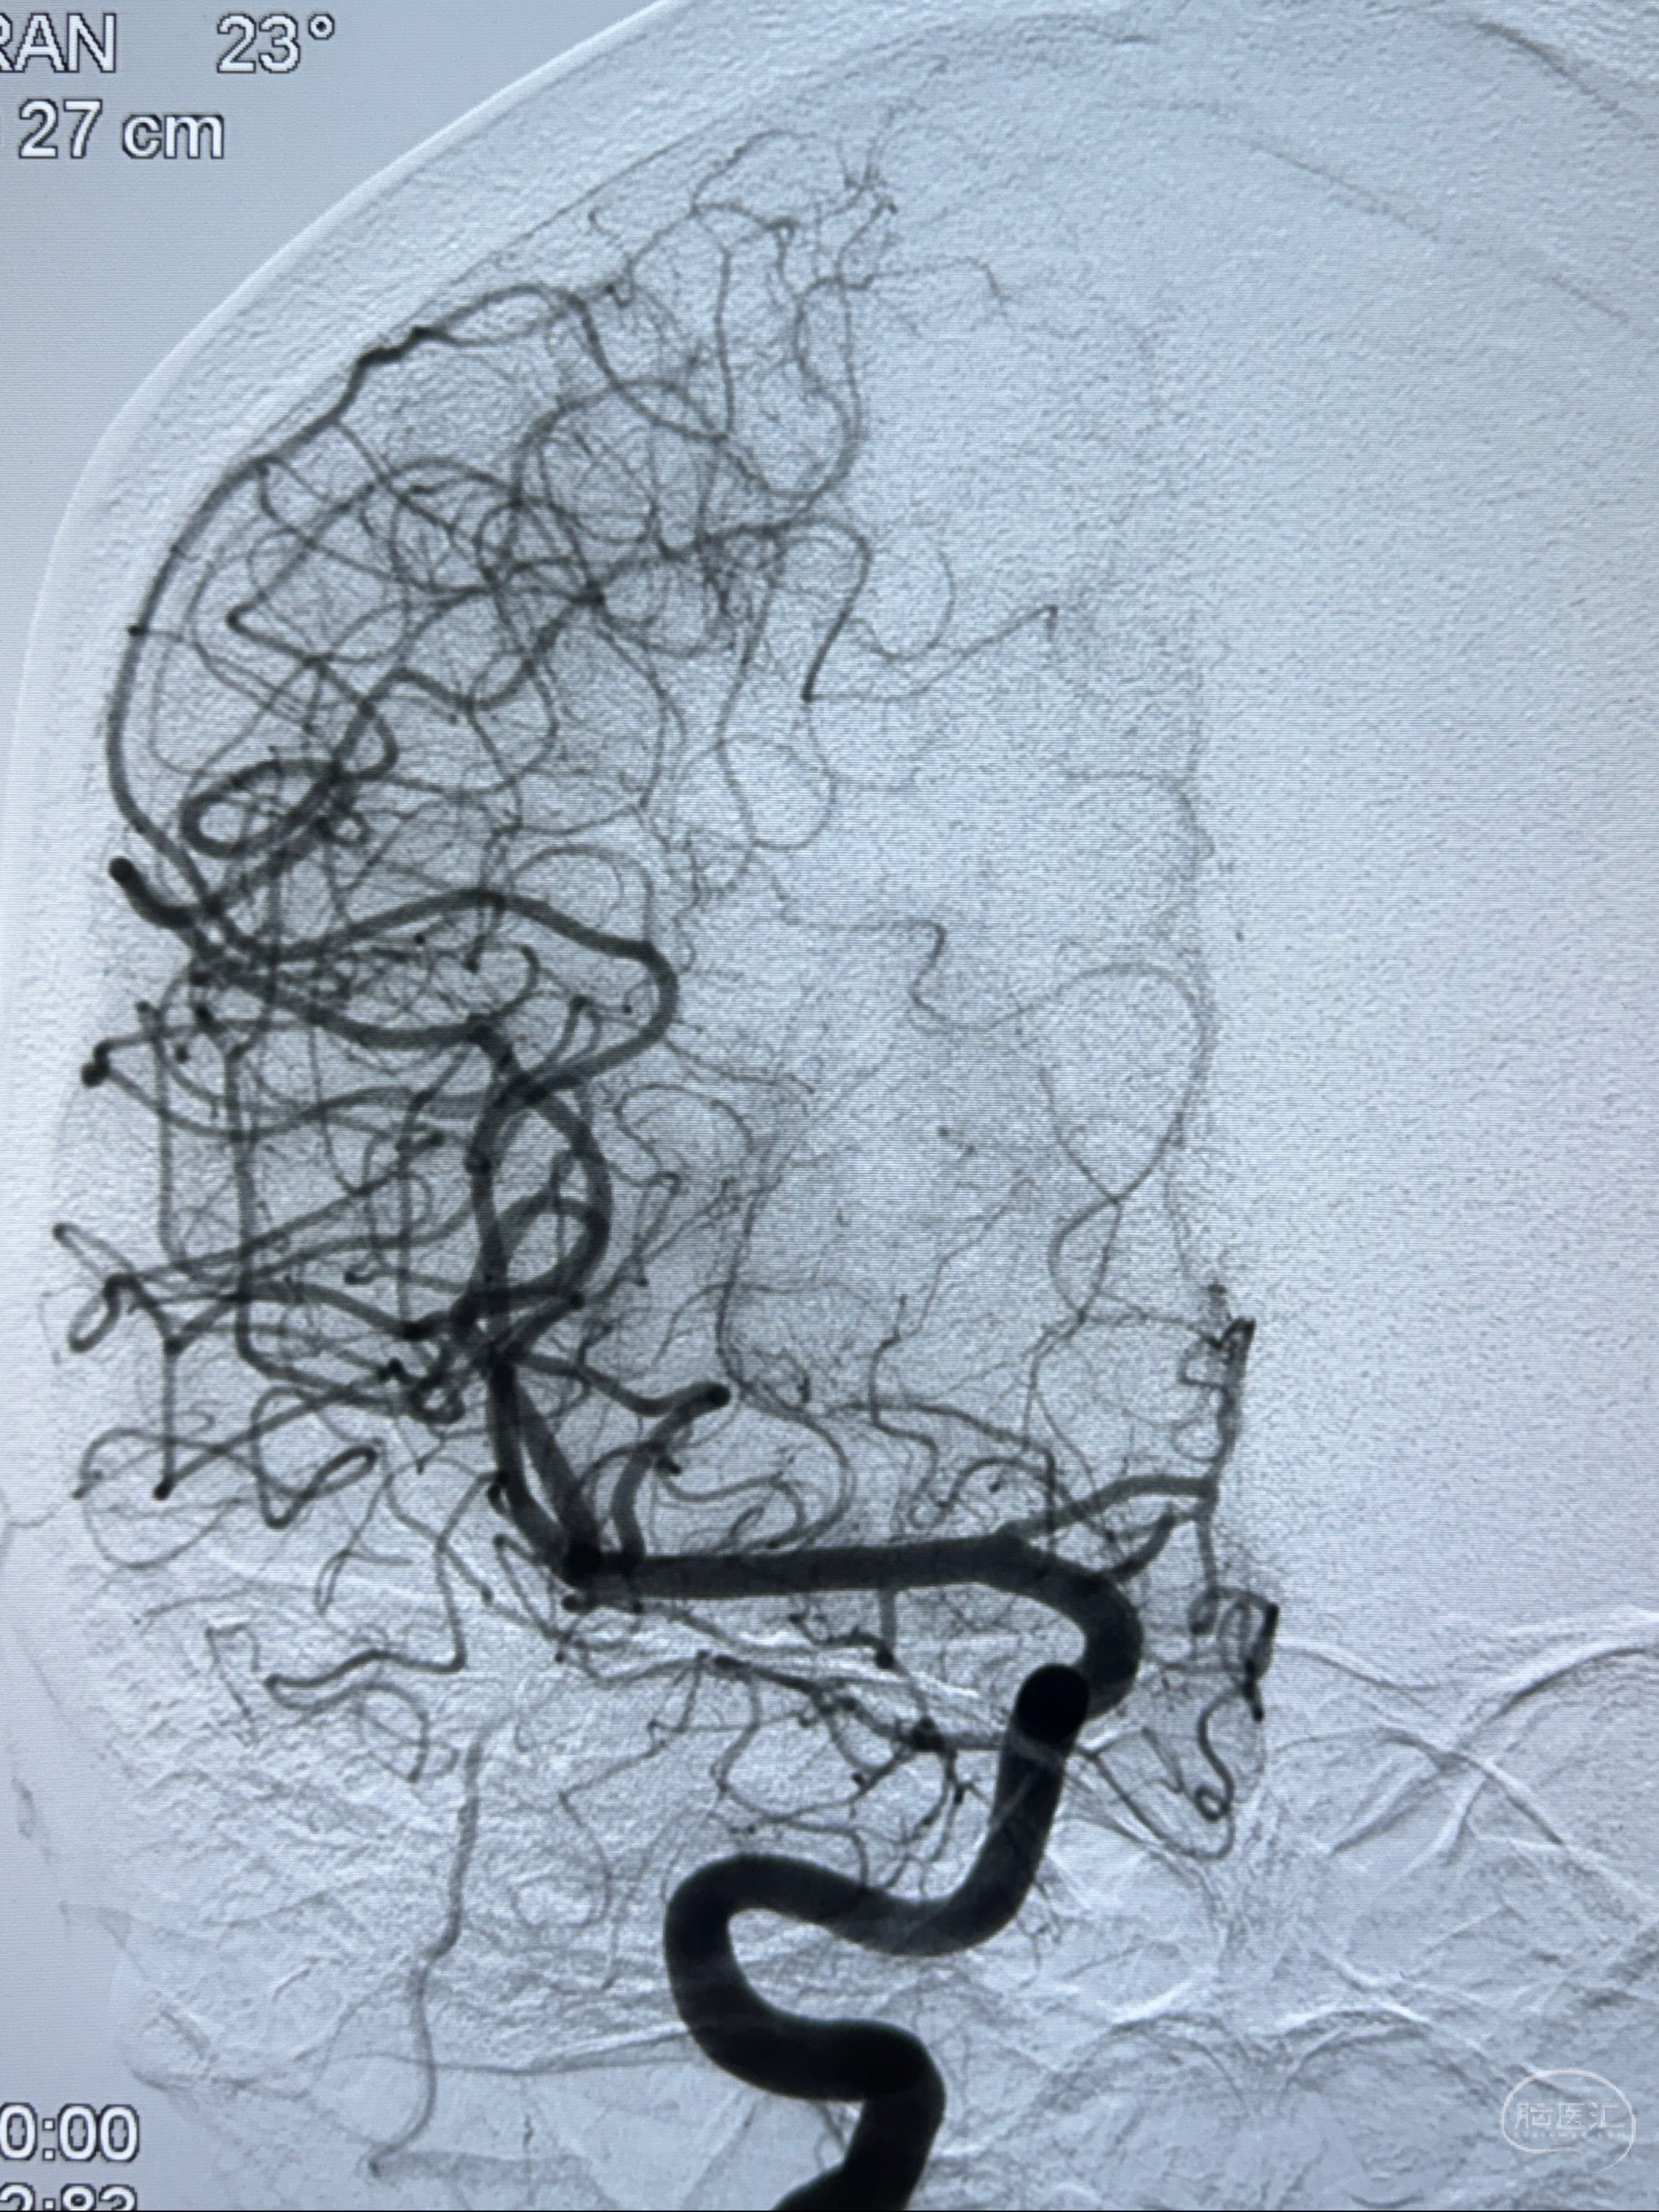

现病史:患者诉近4年来时有头痛发作,服用都梁软胶囊、氟桂利嗪对症治疗一月后症状改善,后头痛较少发作。近3月来患者头痛发作频率明显增加,约一月一次,为右侧偏头痛,胀痛,伴恶心呕吐,呕吐后症状可略减轻;遂于2023-11-01至蓝十字脑科医院就诊,查头颅MRI+DWI+MRA提示:左侧枕叶皮层下小斑片缺血或变性灶,右侧大脑前动脉A1段毛糙,显影淡、纤细,建议完善CTA;并于2023-11-03查头颅CTA提示:左侧颈内动脉C6段微小动脉瘤可能(约2mm),右侧大脑前动脉A1段纤细(对侧优势),左侧大脑中动脉提前分叉。现患者无明显不适,为求进一步诊疗颅内血管病变至我科就诊,收治入院。

2023-11-03 蓝十字脑科医院 头颅CTA:左侧颈内动脉C6段微小动脉瘤可能(约2mm),右侧大脑前动脉A1段纤细(对侧优势),左侧大脑中动脉提前分叉。

1.左侧颈内动脉瘤